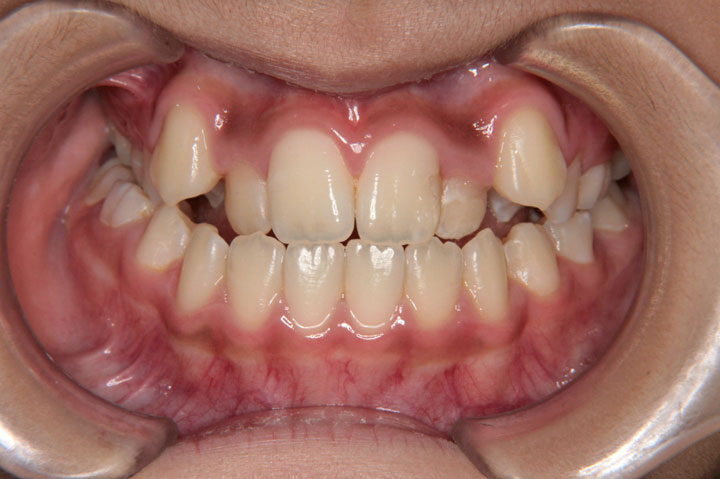

前歯の交叉咬合は、上顎の前歯の一部が、下顎の前歯のよりも内側に入っている状態です。かみ合わせが逆転することで、種々の不利益を引き起こします。通常は、叢生と複合することが多い不正咬合です。お子様の場合、低学年(7~9歳)であっても、交叉咬合と判断される場合は、受診をお勧めいたします。 その時期であれば、比較的良好な治療結果となることが多いと思います。成人の方の治療も可能ですが、負担のかかった歯肉などは、回復できない場合もあります。

症例(40)

【混合歯列 非抜歯】